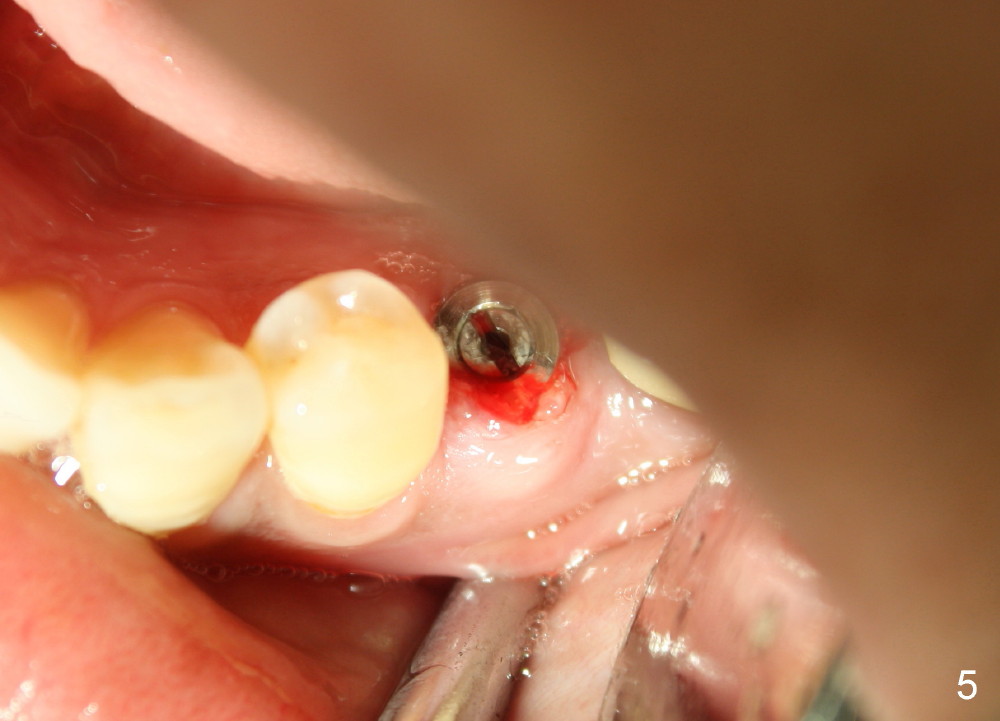

Twelve days post 2nd debridement, the wound does not heal normally. Out of desperation, Arestin is placed incompletely in the mesiobuccal pocket of #19. Fortunately, the wound heals at the site of #20 one month later (Fig.11). No infection is observed 4 months post 2nd debridement (Fig.12,13). Eventually the tooth #19 becomes symptomatic. Extraction and immediate implant is planned. In case the implant at the site of #20 fails, a cantilever bridge is fabricated using the posterior 2 implants.